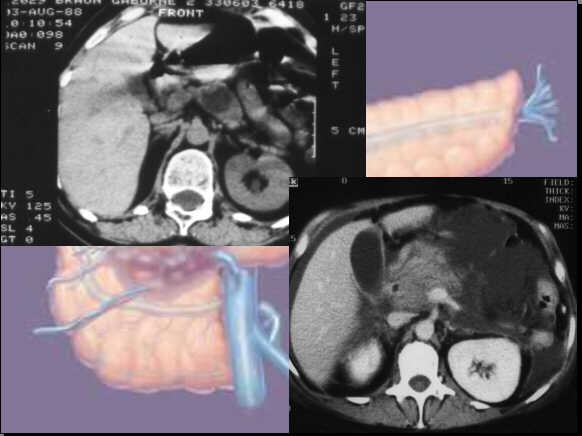

Sometimes the differentiation is easy:

Hypodense well demarcated lesions in the pancreatic body

in native scan: Insular tumour.

Enlarged,

non-homogeneous pancreatic head, peripancreatic fluid

collection: Acute pancreatitis.